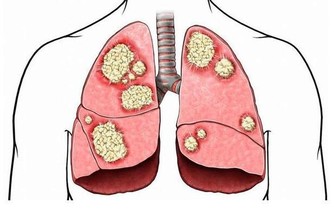

氣促:肺癌的早期跡象

呼吸急促可能是肺癌的表現。

如果咳嗽了好幾周都沒好,不管是乾咳還是咳中帶痰,

都有可能是肺癌的早期跡象,

建議及時就醫,拍X光片、做CT等檢查。